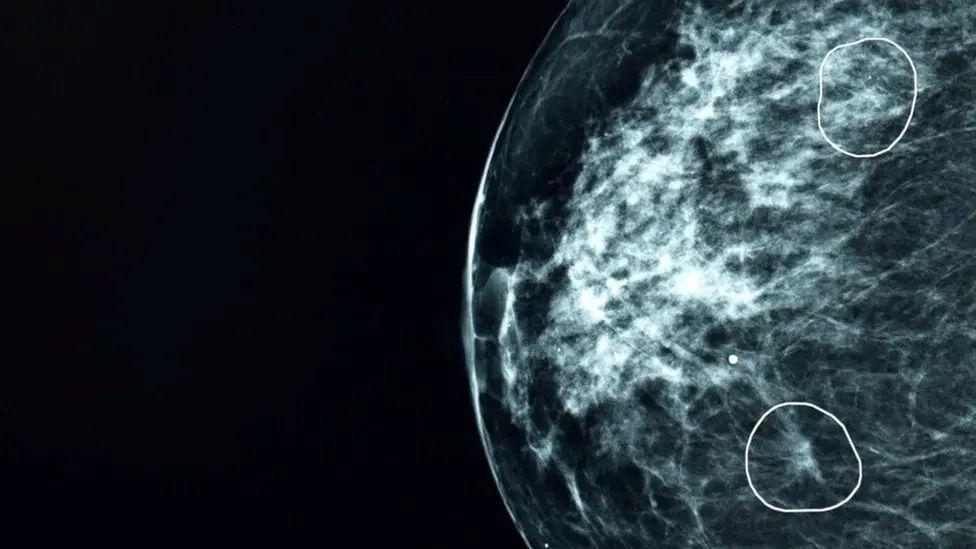

La herramienta de inteligencia artificial Mia marca dos áreas que pueden generar preocupación en una mamografía.

La herramienta de IA busca posibles áreas de preocupación en las mamografías.